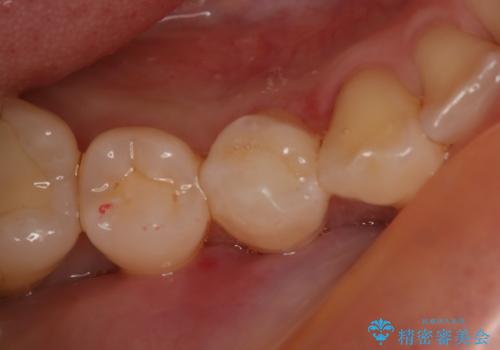

奥歯を白くしたい

- 左上6番の銀歯をセラミックにしたいと希望され来院された患者様です。

切削量を考慮し、セラミックインレーを選択しました。

銀歯を除去したところ虫歯が深かったので、CRを詰めた上で形態を整えています。